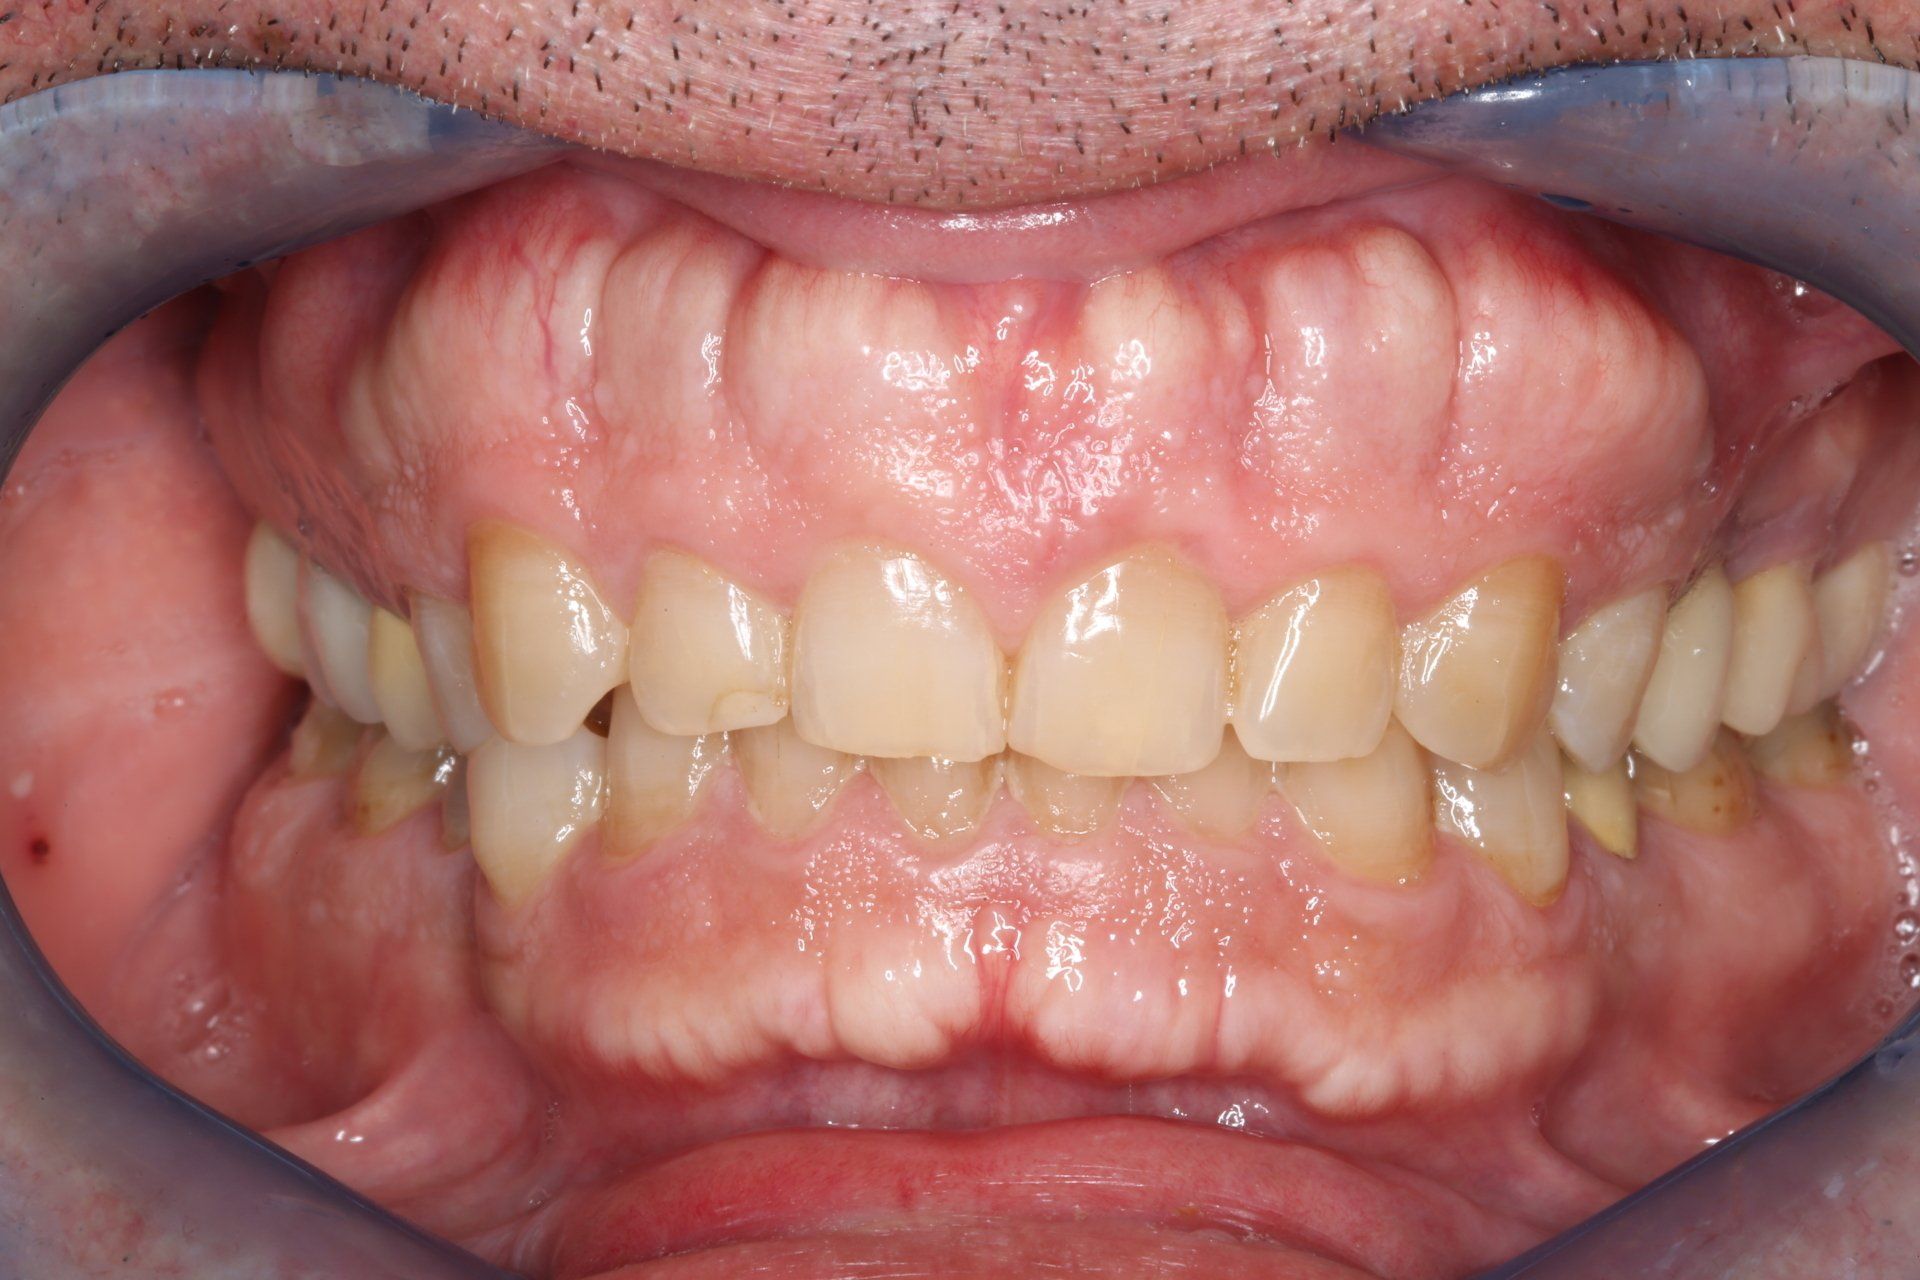

Il paziente si presenta al primo appuntamento (T0) lamentando dolore nella zona degli impianti. A seguito degli esami effettuati è stata diagnosticata una gengivite generalizzata e mucosite perimplantare (Fig. 2, 3, 4).

#dida Fig. 2: Foto frontale T0

Dopo dieci giorni (T1) di utilizzo di PerioTabs®, si è notato un miglioramento dal punto di vista clinico (Fig. 8 e 9). Il P.I. è sceso al 57%, il BoP al 26% e sono diminuite anche le profondità di sondaggio (Fig. 10).

#dida Fig. 8: Foto frontale a T1 prima di FMD